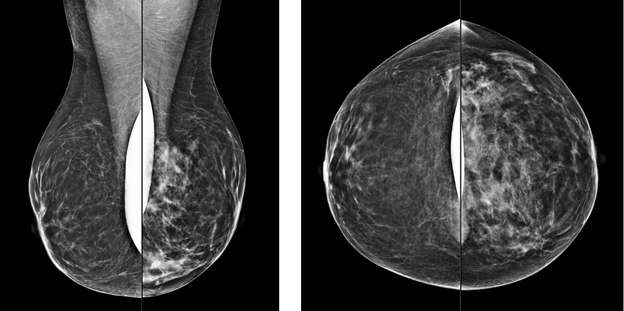

Focal Asymmetry:

A focal asymmetry is a finding seen on two projections3. Focal asymmetries that have been evaluated without suspicious features but persist are likely benign and can be managed with 6-month short-term imaging follow up.

CC views of the breast of the same patient as above demonstrate a correlate to the asymmetry seen on MLO view. This is now a focal asymmetry of the left breast at 3 o’clock.